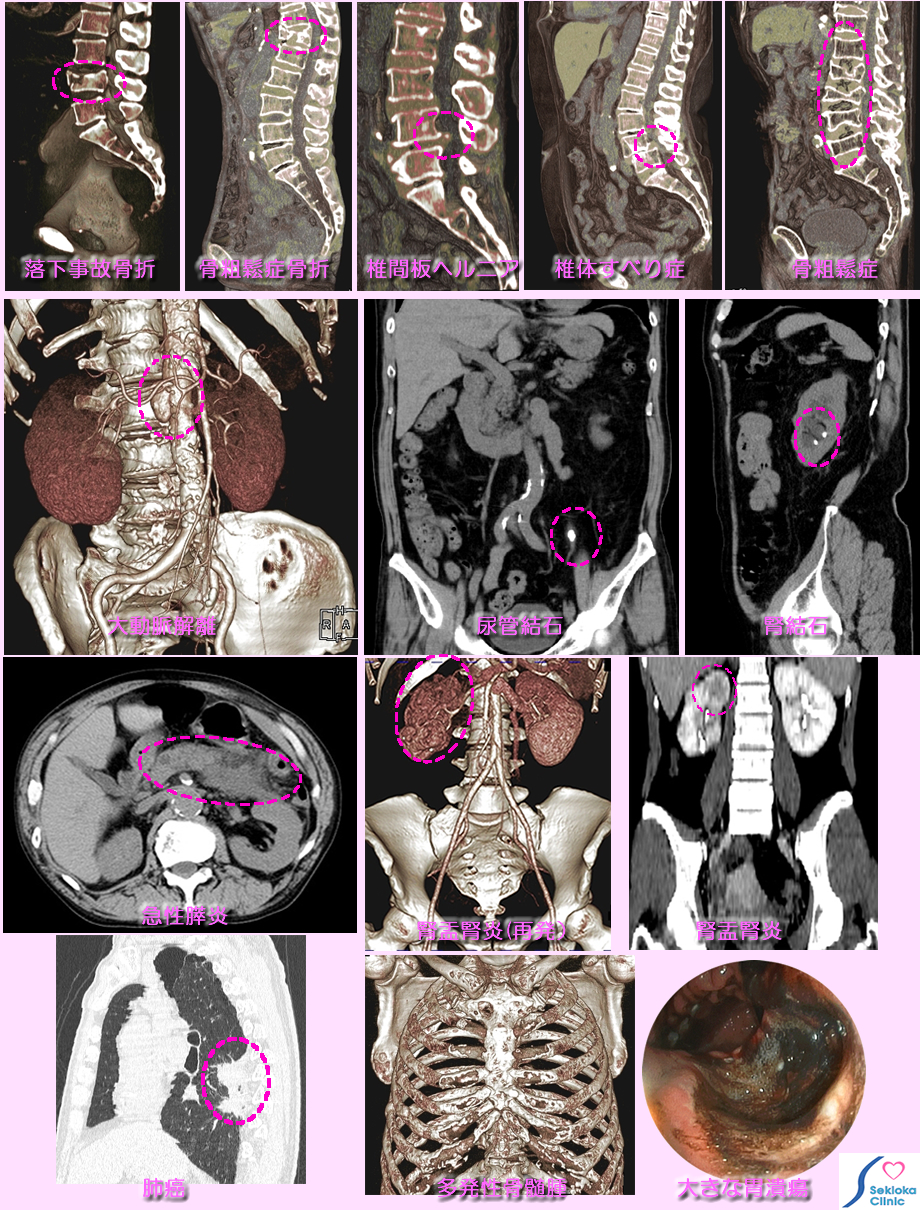

| 診断 | 腰痛、背部痛を生じる代表的疾患の診断画像を添付します。脊椎の異常では従来、X線撮影、CTが使われていましたが、最近は3次元的観察が可能で 任意断面の画像が得られるMDCT、MRIが詳細な評価に有用です。上段は腰痛・背部痛で検査したMDCTによる腰椎・胸椎の断面画像です。各原因疾患の鑑別と重症度を評価します。2段目左は、腰痛で受診され、超音波エコーで検査した結果、腹部大動脈の解離が疑われ、造影MDCTで精査を行い確診に到った例です。2段目中央は背部痛で整形外科を受診されレントゲン検査で脊椎に異常無しと診断されましたが、痛みが続くため受診されMDCT検査で尿管結石と診断された例です。2段目右は腎結石の例です(白色が石)。3段目左は背部痛、腹痛を訴えられた急性膵炎、3段目中央と右は背部痛と発熱で受診され、検査の結果、腎盂腎炎と診断された例です。最下段左は背部痛で受診され、肺癌と診断された例、最下段中央は胸部痛、背部痛で当初、整形外科を受診され、その後当院を受診され多発性骨髄腫と判明した症例、最下段右は腰背部痛で受診された、巨大な胃潰瘍の例です。 |